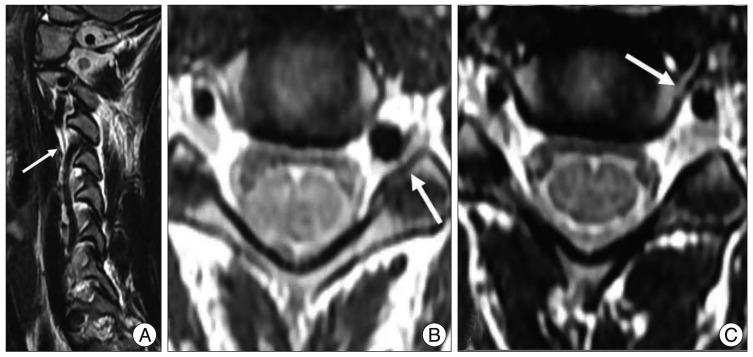

It is rare that the medial loop in the V2 segment of the vertebral artery (VA) causes compression of the proximal cervical root of the spinal cord without leading to bony erosion and an enlarged foramen. We evaluated the clinical significance and incidence of the medial loop in the V2 segment of the VA.

We reviewed the records from 1000 consecutive patients who had undergone magnetic resonance imaging evaluation of the cervical spine between January 2005 and January 2008. The inclusion criteria were that over a third of the axial aspect of the VA located in the intervertebral foramen was inside the line between the most ventral points of the bilateral lateral mass, and that the ipsilateral proximal root deviated dorsally because of the medial loop of the VA. We excluded cases of bone erosion, a widened foramen at the medial loop of the VA, any bony abnormalities, tumors displacing VA, or vertebral fractures. The medical records were reviewed retrospectively to search for factors of clinical significance.

In six patients (0.6%), the VA formed a medial loop that caused compression of the proximal cervical root. One of these patients had the cervical radiculopathy that developed after minor trauma but the others did not present with cervical radiculopathy related to the medial loop of the VA.

The medial loop of the VA might have a direct effect on cervical radiculopathy. Therefore, this feature should be of critical consideration in preoperative planning and during surgery.